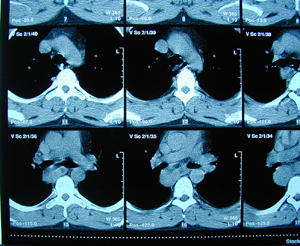

Εικόνα 2 α-γ

Αξονική τομογραφία του θώρακος σε διαφορετικά επίπεδα. Διακρίνεται η παρουσία όγκου στο οπίσθιο μεσοθωράκιο που πιθανά να αποτελεί όγκο του οισοφάγου.